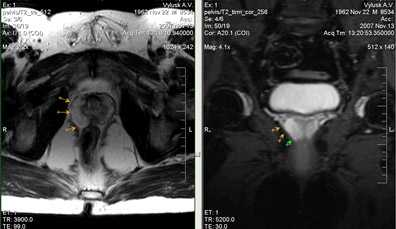

9. Везикулит.

Везикулит - это воспаление семенных пузырьков. Клинически характерно появление болей над лобком и в промежности, которые отдают в поясницу, пах или крестец. Боли усиливаются при дефекации и позывах на мочеиспускание. При дефекации бывает также выделение из уретры слизистого содержимого, иногда с прожилками крови - это секрет пузырьков. Кроме того, при везикулите становится болезненной эякуляция и в сперме появляются следы крови. Наблюдается расстройство эрекции. Страдает и общее состояние: характерны слабость, головная боль, повышенная утомляемость и температура. Часто обостряются и сопутствующие симптомы простатита.

Рис. 40 а)Т2-tra б) Т1-tra +контраст

Мужчина, 34 лет с гематоспермией. Преконтрастные Т2-ВИ (а) и постконтрастные Т1-ВИ изображения (б) в аксиальной плоскости демонстрируют диффузное утолщение стенок семенных пузырьков, неоднородность их внутренней структуры.